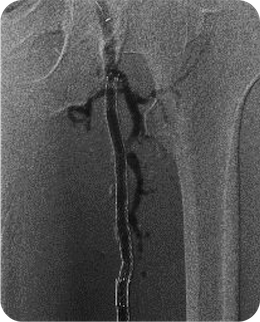

腎障害のある方への炭酸ガス造影に関して

カテーテル検査、治療には、通常造影剤という薬剤を血管に注入する必要があります。

しかし造影剤には腎臓に対する毒性やアレルギー反応という問題があり、重篤な腎機能障害を有していたり、過去に造影剤にて重篤なアレルギー症状を来したことのある患者さんには使用が困難です。

そこで当院では、こういった患者さんに対してのみ、生体に影響が少ないとされる炭酸ガスを造影剤の代わりに用いています。

炭酸ガスは酸素に比して約20倍も血液に溶け、そのほとんどが投与後すぐに体外に排出されます。

低侵襲性、低コスト、そして何よりも無腎毒性、無アレルギー性を最大の利点としています。

通常の造影剤より画像の鮮明さという点で劣り、完全に通常の造影剤に取って代わることはできませんが、炭酸ガスを用いることによって通常の造影剤の量を減量することも可能です。 また炭酸ガス造影に血管内超音波検査などの血管内イメージ機器を併用することにより更に造影剤の低減が可能です。

冠動脈や脳動脈など、短期的な虚血でも強い症状が出現する臓器への使用は困難ですが、主に下肢などの下半身の血管造影の際に施行しています。

炭酸ガスによる大腿動脈の造影

通常の造影剤による大腿動脈の造影